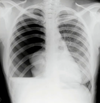

Image 1

Left-sided Massive Pleural Effusion

With contralateral shift of mediastinum and trachea.

Most common cause of non-traumatic massive pleural is cancer.